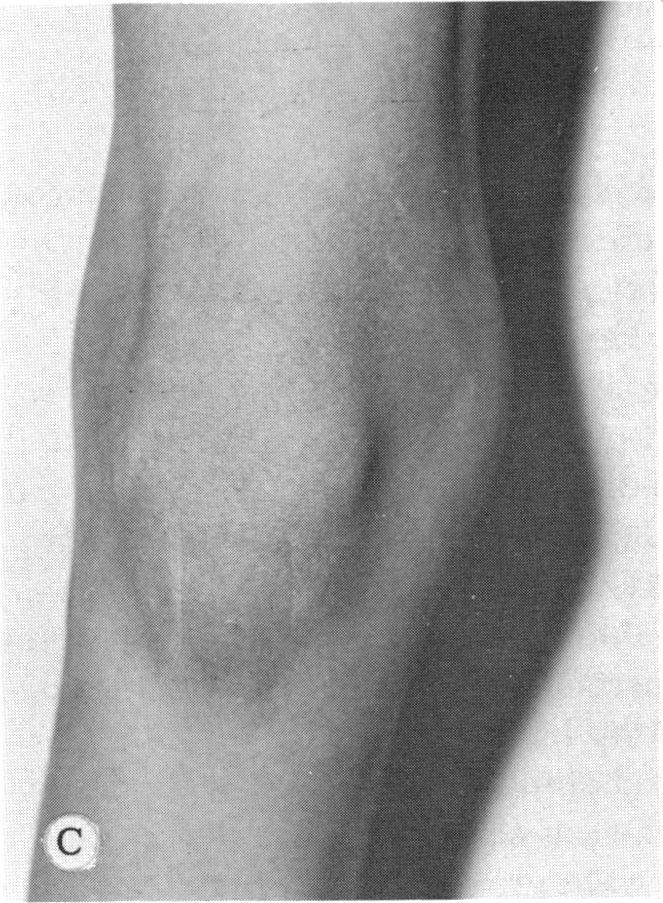

遗传性玻璃体视网膜病变和骨骼发育异常。

Inherited hyaloideoretinopathy and skeletal dysplasia.

Twenty-one patients from five families displaying the ocular defects of dominantly inherited hyaloideoretinopathy as originally described by Wagner were surveyed radiographically for skeletal defects. A mild generalized epiphyseal dysplasia was found in twenty. A comparison of the skeletal dysplasia associated with arthro-ophthalmopathy and that found in families with Wagner's disease reveals more similarities than differences. It is concluded that Wagner's disease is a dominantly inherited syndrome of ocular defects that includes myopia, vitreous syneresis with membranes, and radial perivascular chorioretinal degeneration. It is associated with radiographically demonstrated generalized epiphyseal dysplasia that is manifested clinically by flattening of the mid-face and palatoschisis.

对来自五个家族的21名患者进行了X线检查,以确定是否存在骨骼缺陷。这些患者表现出如Wagner最初所描述的显性遗传性玻璃体视网膜病变的眼部缺陷。在20名患者中发现了轻度全身性骨骺发育异常。对与关节眼病相关的骨骼发育异常和瓦格纳病家族中发现的骨骼发育异常进行比较,结果显示相似之处多于不同之处。得出的结论是,瓦格纳病是一种显性遗传的眼部缺陷综合征,包括近视、伴有膜的玻璃体脱离和放射性血管周围脉络膜视网膜变性。它与X线检查显示的全身性骨骺发育异常有关,临床上表现为中面部扁平及腭裂。